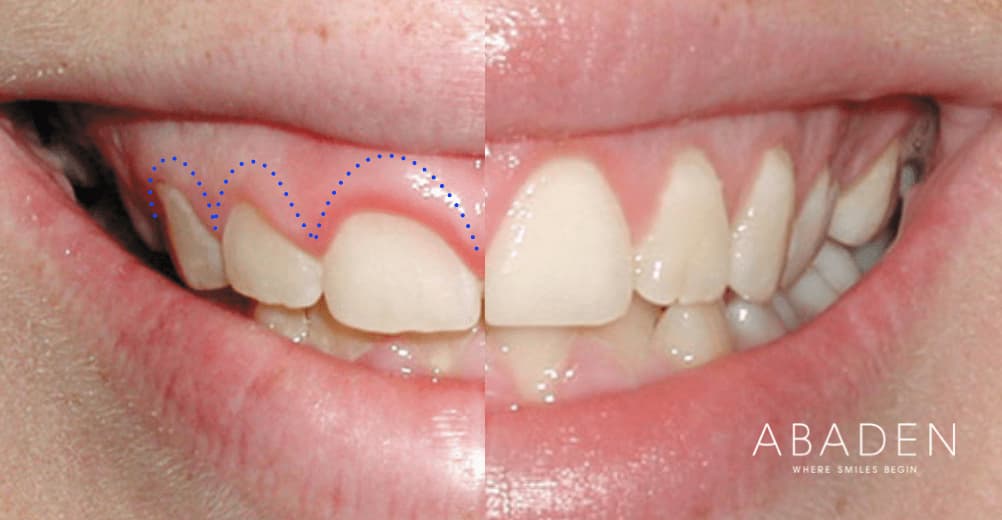

corona dental antes y despues Alargamiento coronario: ¿qué es y cómo se hace?

Alargamiento Coronario: ¿qué Es Y Cómo Se Hace? | Abaden